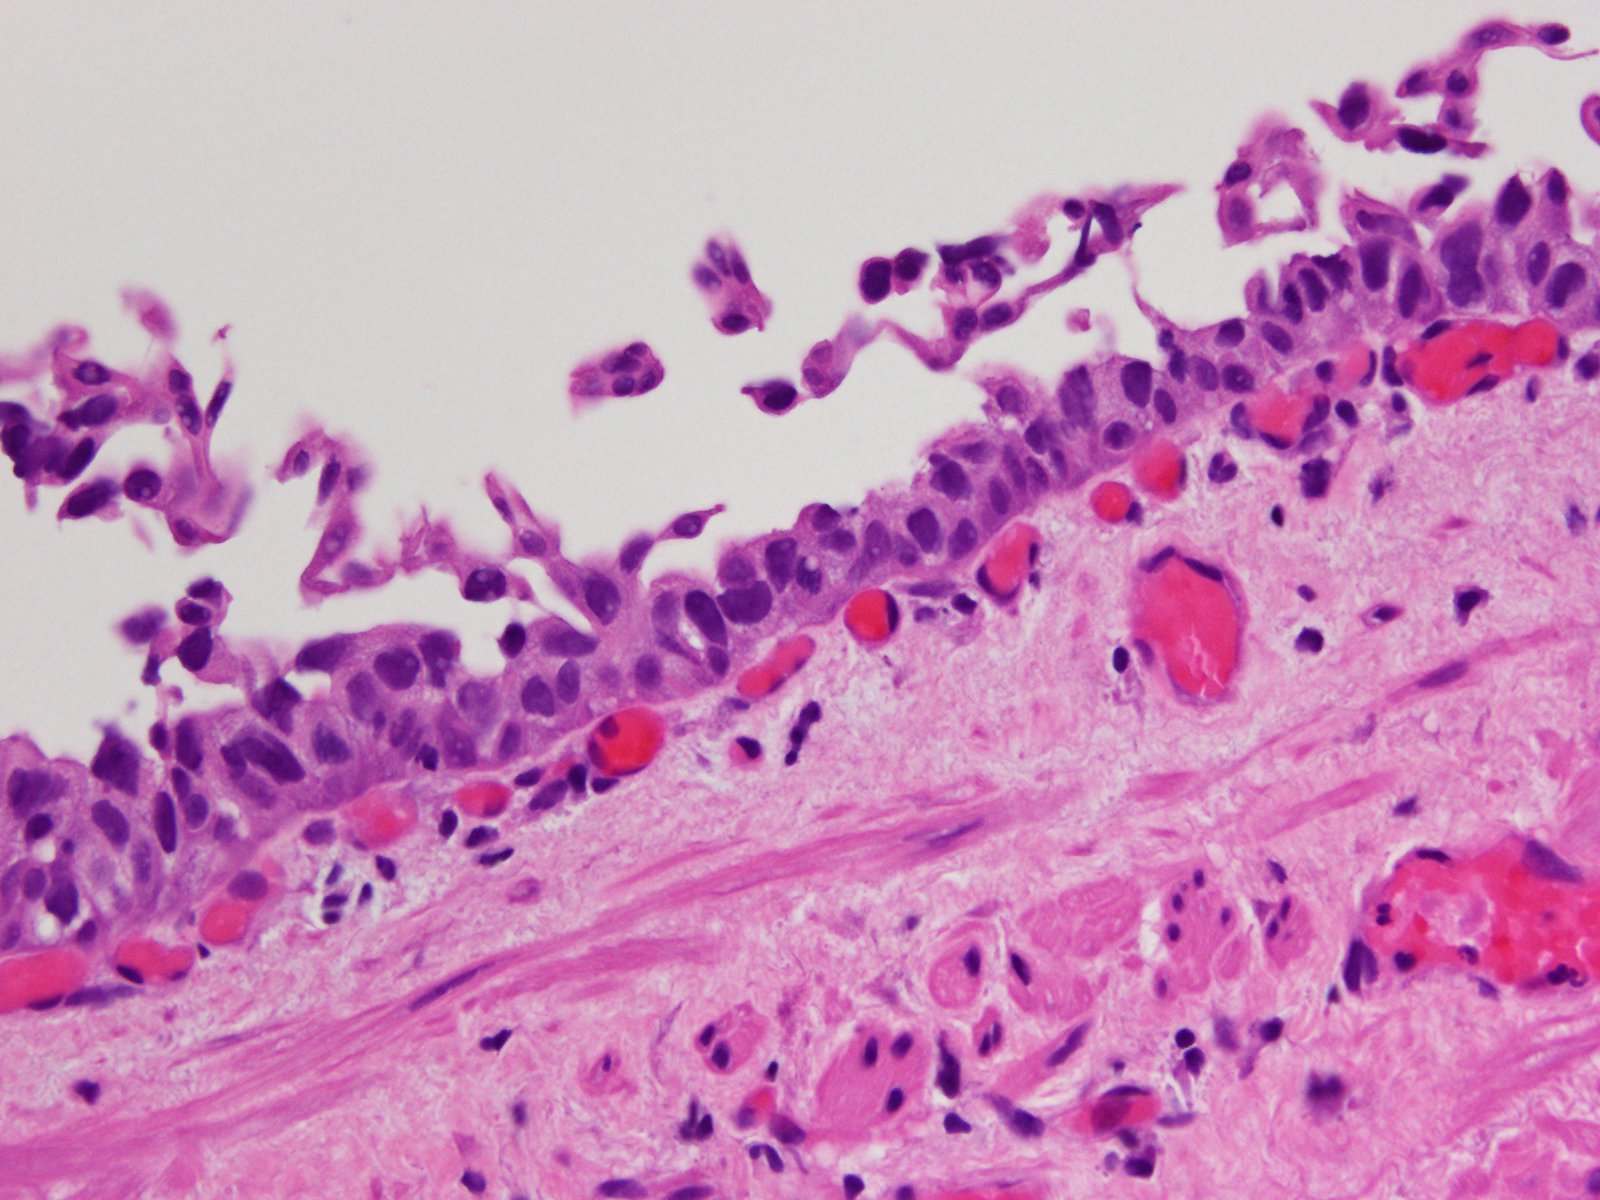

Bladder Flat Lesions

Case ID: 94

Reactive atypia

Atypia/dysplasia

Carcinoma in situ (CIS)